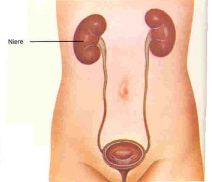

Nieren,

Harnleiter und Harnblase, Schema [6].

Es ist nur logisch, dass sich das

Quecksilber des Amalgams in den Nieren

anreichert, weil die Niere ja das Blut

reinigt, und so sind Nierenschäden

eigentlich nur logisch...